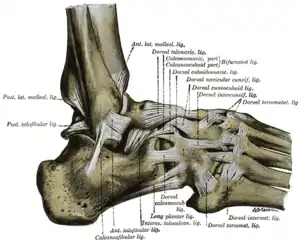

The ligaments of the foot from the lateral aspect. (Calcaneocuboid labeled at top, third from right.) | |

Ligaments

There are five ligaments connecting the calcaneus and the cuboid bone, forming parts of the articular capsule:

- the dorsal calcaneocuboid ligament.[2]

- part of the bifurcated ligament.[2]

- the long plantar ligament.[2]

- and the plantar calcaneocuboid ligament.[2]